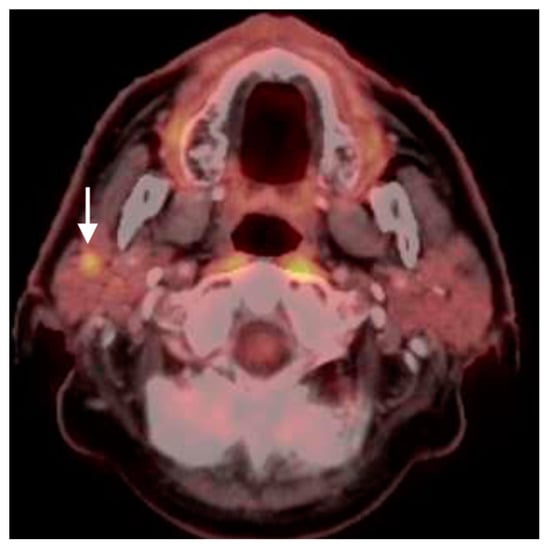

2.5. Major and Minor Salivary Gland, Lacrimal Gland Tumors

- Pleomorphic adenoma and carcinoma ex pleomorphic adenoma

- 2.

- Warthin tumor

- 3.

- Mucoepidermoid carcinoma

- 4.

- Adenoid cystic carcinoma

2.6. Thyroid Cancer